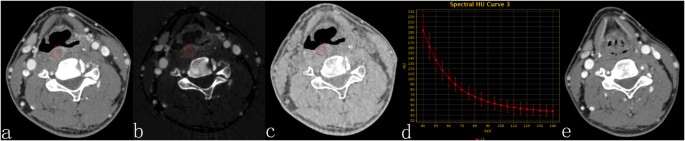

The results of the statistical analysis of the quantitative GSI parameters indicated that the sIC, λHU, and Zeff of the CR group were significantly lower than that of the NCR group, while there was no significant difference in the sWC between the two groups (Table 2). The mean sIC (P < 0.00), λHU (P < 0.00), and Zeff (P < 0.02) for the CR group were (20.51 ± 5.092 [standard deviation]) × 10−2, 1.96 ± 0.52 and 8.51 ± 0.20 VS (30.41 ± 9.61) × 10−2, 2.72 ± 0.64, 8.71 ± 0.29 for the NCR group. In addition, the mean sWC (P > 0.05) for the CR group was (1005.59 ± 6.67) × 10−3 VS (1003.98 ± 11.41) × 10−3 for the NCR group (Table 2, Figs 1 and 2).

54Y, M, hypopharyngeal squamous cell carcinoma. Contrast-enhanced GSI images before CRT (a,b,c) and three months after therapy. (a) The 70-keV monochromatic image shows posterior pharyngeal wall cancer. (b) The iodine-based material-decomposition image shows that the IC-L of the ROI is 15.11·100 μg/cm3 (sIC = 0.18). (c) The water-based material-decomposition image shows that the WC-L of the ROI is 1033.43 mg/cm3 (sWC = 1.00). (d) Spectral HU curve of ROI; λHU was 1.92. (e) The 70-keV monochromatic image shows that the mucous membrane of the posterior pharyngeal wall is smooth, and the response assessment is CR.